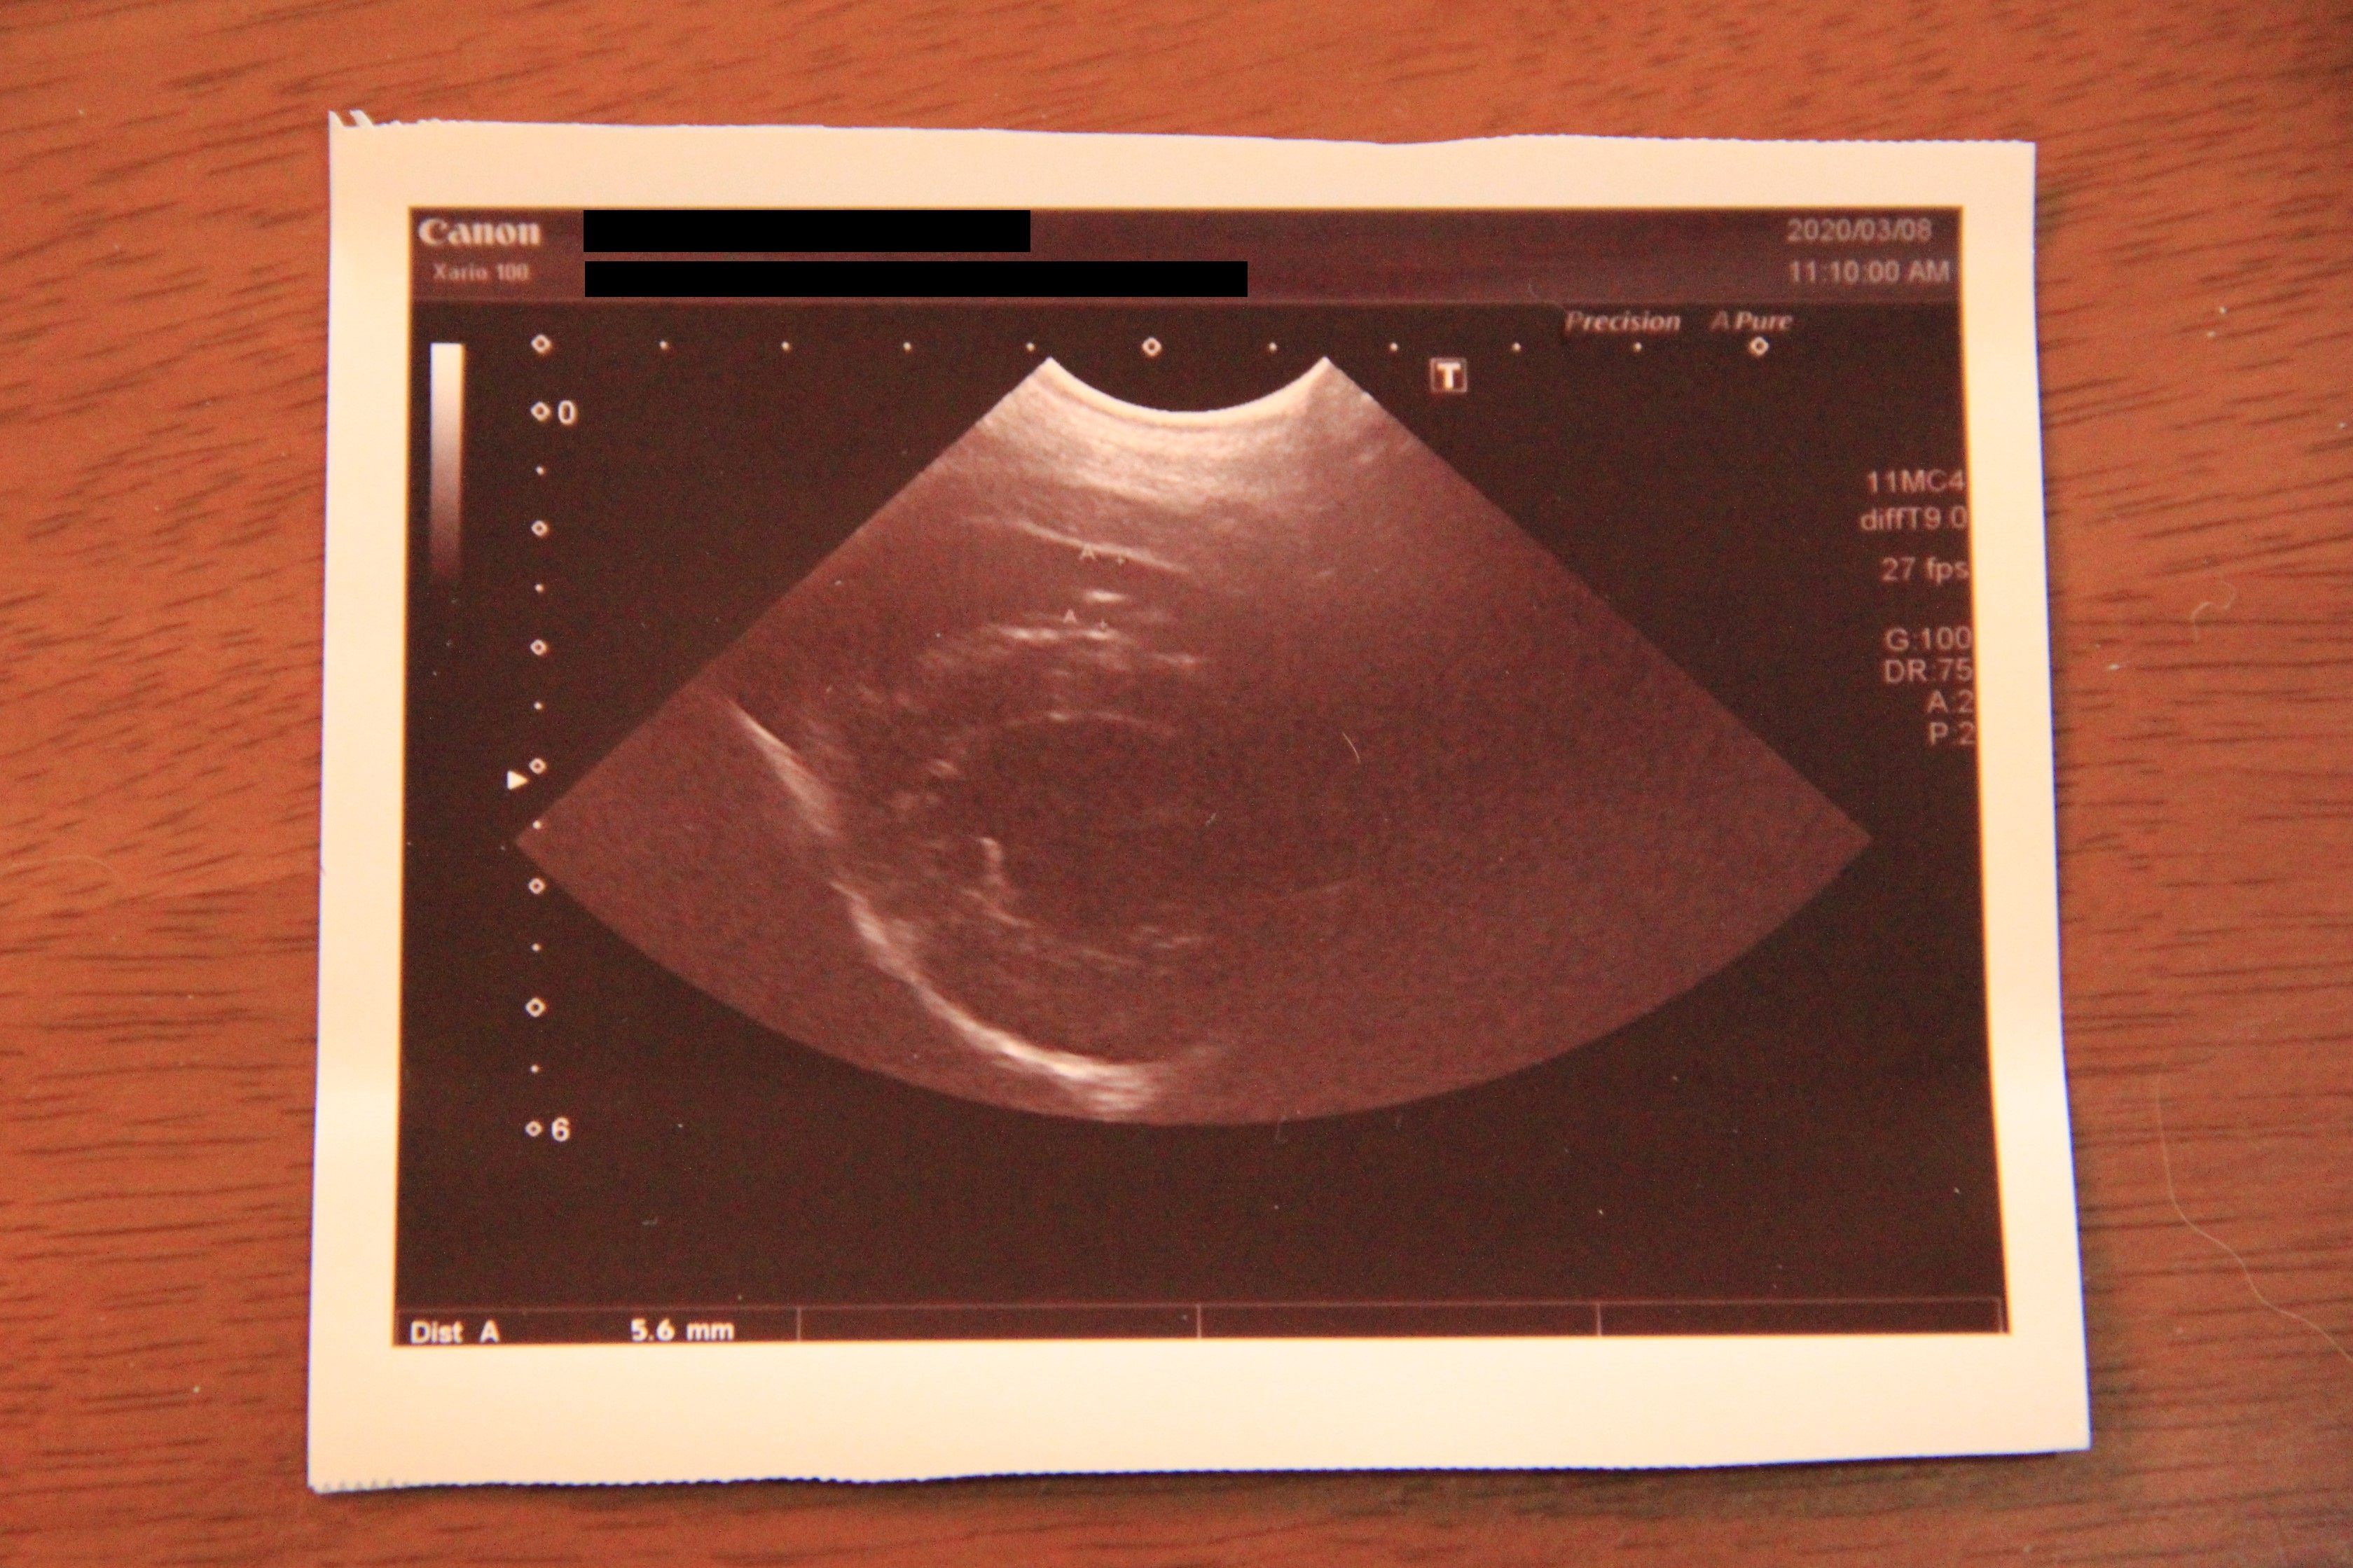

【3/8、『心臓血管肉腫による心タンポナーデ』5日後】

エコーで見たところ、血液の量は退院した時と変わらないですね

次回また1週間後かな、エコーで見てみましょう

心臓と心膜の間の血の量が増えていなかったのでひと安心。